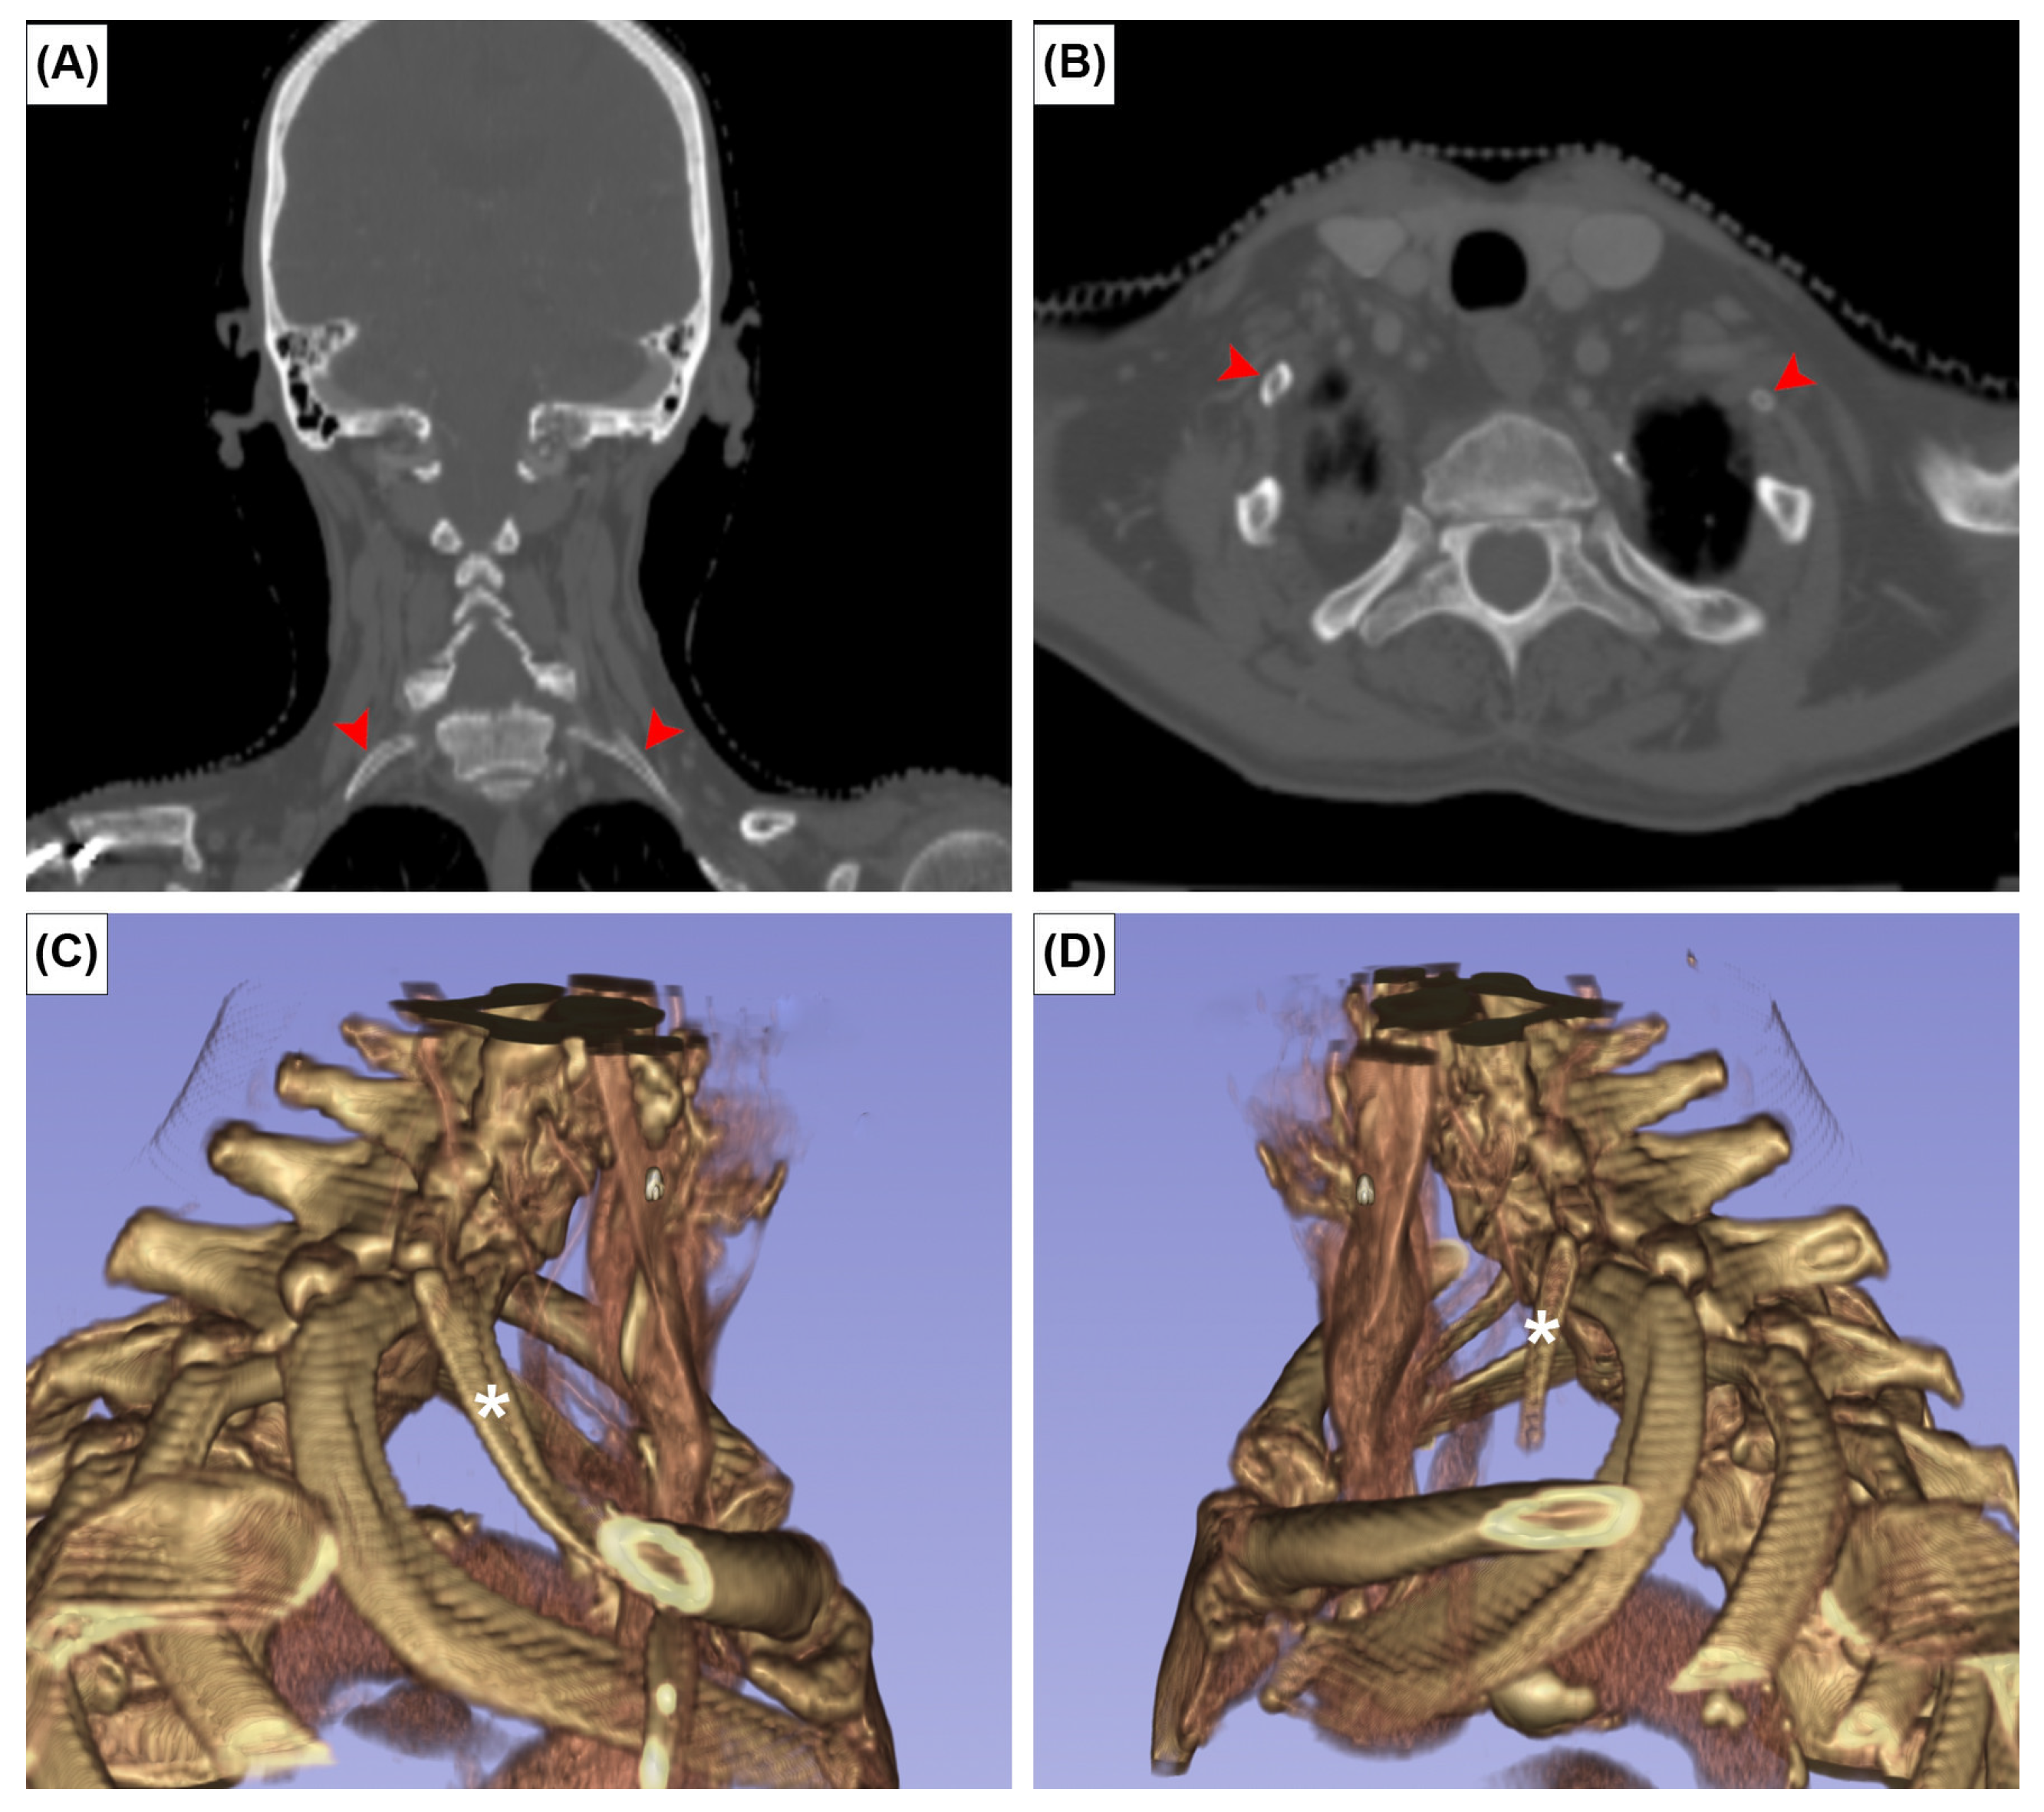

The EOs were present at the posterior surface of the manubrium in 12 cases (2.0%). It was unilateral in seven sterna (58.3%) (Figure 2A,B) and bilateral in five (41.7%) (Figure 2C). The CR was found bilaterally in one patient (0.2%) (Figure 3). In this patient, the left CR was approximately 40 mm long and did not articulate with any other structure. The right CR was approximately 60 mm long. It coursed anteriorly and inferiorly to reach the manubrium, but did not articulate with it.

Figure 3. Coronal (A), axial CT images (B) and three-dimensional reconstruction of right (C) and left (D) cervical ribs. Red arrowheads and asterisks indicate the cervical ribs.